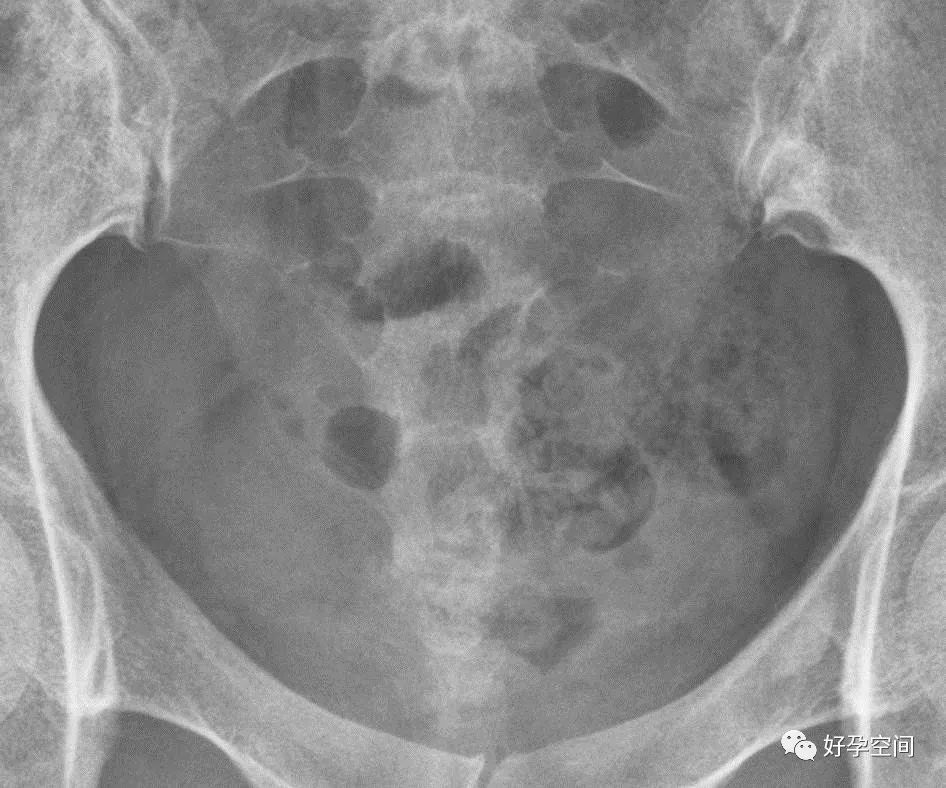

平片,盆腔内可见片状、点状及不规则形高密度影